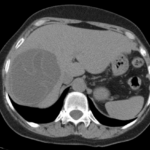

El diagnóstico se basa en hallazgos clínicos, serológicos y de imágenes. La ecografía tiene una sensibilidad del 90-95% (Silva et al., 2006), mientras que la tomografía computada (TC) y la resonancia magnética (RM) ofrecen mayor especificidad anatómica para definir número, ubicación y complicaciones, así como para caracterizar la extensión extrahepática (Maeda et al., 2021; Singh et al., 2001). El realce de contraste suele ser escaso o nulo, reflejando la baja vascularidad de la lesión (Patnana et al., 2018).

- Órgano afectado: hígado: 146 (90,7%); pulmón: 5; bazo: 5; riñón: 3; vesícula: 1; estómago: 1.

- Clasificación de Gharbi: tipo I: 16,4%; tipo II: 11%; tipo III: 6,8%; tipo IV: 13,7%; tipo V: 52,1% (calcificados).